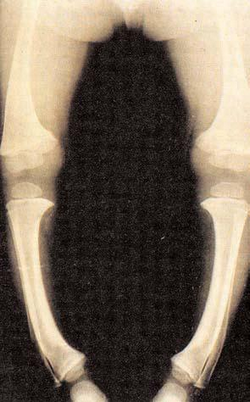

3-6/ Le rachitisme

Il est dû au fait que l’enfant manque de vitamine D et qu’il a marché trop longtemps sur des os fragiles.